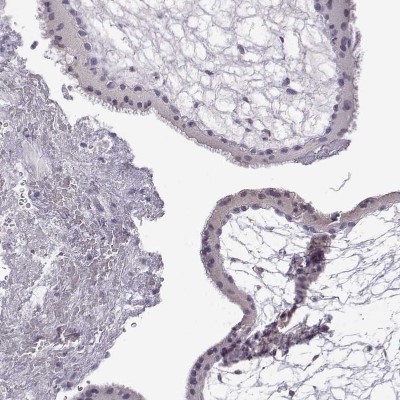

- Immunohistochemistry-Paraffin: VGF Antibody [NBP2-31596] - Staining of human testis.